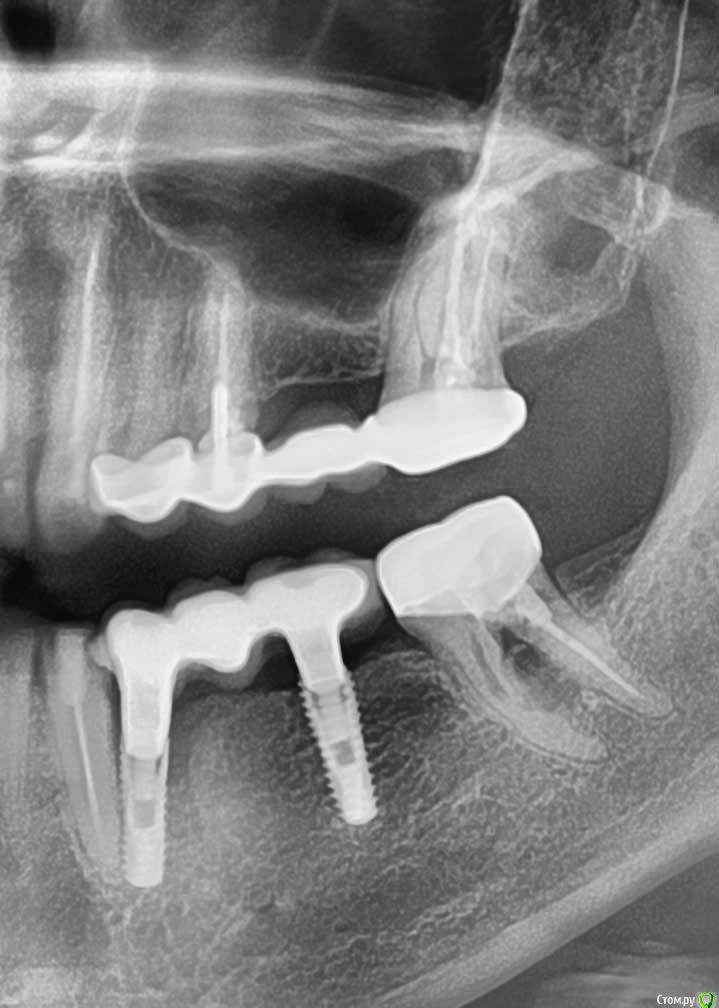

В апреле 2020 года была проведена имплантация на месте 34 и 36 зубов (корейская система INNO implant submerged 3.5x12, 4.0х12).

В июле 2020 года на импланты был установлен металлокерамический мост на приливаемых абатментах (винтовая фиксация). По состоянию на 20.11.2020 (4 месяца под нагрузкой) жалоб не было.

22.01.2020 ослабли винты на имплантах, был сделан новый снимок, где обнаружилось, что имплант на месте 36 сломался.

Снимки прилагаю.

post-62133-0-85066500-1611750715_thumb.jpg